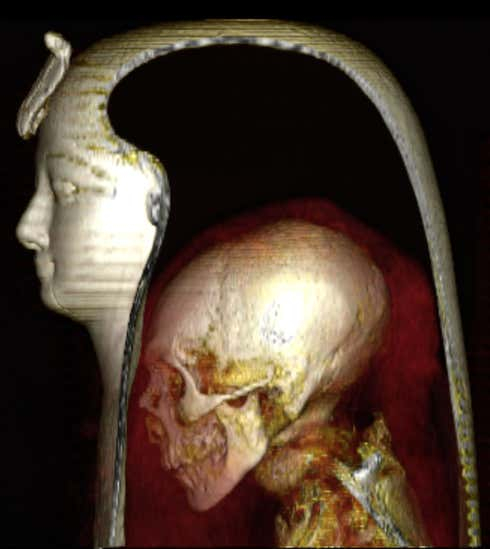

Ninguém viu o rosto do Faraó Amenhotep I por cerca de 3.000 anos – até recentemente. Os cientistas usaram tecnologias de pesquisa não invasivas para obter uma visão precisa dos restos mortais escondidos em um sarcófago lacrado – para isso, eles tiveram que recorrer à tomografia computadorizada (TC).

A julgar pelos materiais publicados na revista Frontiers in Medicine, a tomografia computadorizada possibilitou determinar a aparência da antiga régua – milhares de “fatias” combinadas em um único modelo digital permitem representar com precisão a aparência de Amenhotep. A tecnologia já foi usada duas vezes neste ano para pesquisar múmias.

Como resultado da varredura, cerca de 30 amuletos e um cinto feito de contas de ouro foram encontrados no corpo do faraó. Os cientistas não encontraram sinais de que o faraó morreu devido a ferimentos ou qualquer doença que alterasse seriamente. O corpo foi danificado, mas os pesquisadores sugerem que os responsáveis por isso foram os ladrões de túmulos, que abriram o sarcófago após o sepultamento. Em particular, a integridade dos tecidos na região do pescoço e extremidades é violada – como relatam os cientistas, é aqui que geralmente se encontram as joias.

Descobriu-se que a múmia manteve alguns dos cachos cacheados e os dentes estavam no lugar. Acredita-se que durante o reinado de Amenhotep, o Egito Antigo atingiu o auge de seu poder e desenvolvimento, incluindo o uso de tecnologias de mumificação perfeita. Todas as múmias pertencentes a este período estão perfeitamente preservadas.

O cérebro e o coração do Faraó ainda estão no lugar. Na comunidade científica, acredita-se que os órgãos internos geralmente eram retirados para evitar a decomposição do corpo, exceto o coração – os antigos egípcios acreditavam que ele servia como uma espécie de “recipiente” para a alma.